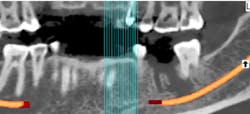

In summation, the best treatment for nerve injury continues to be prevention. If there is any doubt by the treating clinician as to the proximity of an odontogenic lesion to the nerve space (figure 4), a CT scan prior to extraction therapy is the gold standard of care (figure 5). This pretreatment diagnostic can avoid both clinical and legal headaches.

Figure 4: Another case demonstrating periapical pathology and its proximity to the IAN

Figure 5: Preoperative CT scan obtained prior to tooth extraction to prepare for surgery and limit the possibility of nerve violation